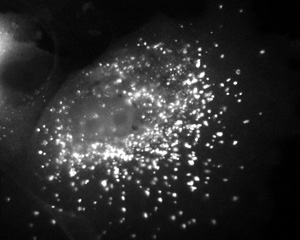

Debnath is trying to answer this question in tumor-causing milk duct cells from the breast, using genetic strategies to change levels of autophagy. Autophagy and Drug Resistance Manipulation of autophagy might be used to bolster the power of chemotherapy drugs. Many cancer treatments, Debnath explains, result in huge increases in autophagy in the cancer cells. Scientists are not sure why cancer cells dial up autophagy when hit with drugs. And few assume that all cancers will act in the same way when it comes to autophagy and chemotherapy. But already, while studying deadly brain cancer cells rather than breast cancer cells, UCSF researcher Russ Pieper, PhD, and his collaborators recently found that DNA-damaging chemotherapy caused the cells to become resistant to treatment by switching on autophagy. Turning on autophagy allowed these cells to produce more usable energy, in the form of a molecule called ATP. Increased production of ATP made possible by autophagy was associated with increased cell survival. More tumor cells died when the researchers countered by adding a drug that blocks autophagy. "Our understanding of autophagy has exponentially increased in the last few years and has broached the exciting possibility of using 'self-eating' as a therapeutic strategy to curtail tumor cell survival and expansion," Debnath concludes. Does Autophagy Contribute to Cell Death? Jayanta Debnath, Eric H. Baehrke and Guido Kroemer Autophagy 1(2):66-75, July/August/September 2007 Abstract | Full Text (PDF) DNA Damaging Agent-Induced Autophagy Produces a Cytoprotective Adenosine Triphosphate Surge in Malignant Glioma Cells M. Katayama, T. Kawaguchi, M.S. Berger, R.O. Rieper Cell Death and Differentiation 14(3):548-558, March 2007 Full Text | Full Text (PDF) Related Links: Jayanta Debnath, MD Pieper Laboratory